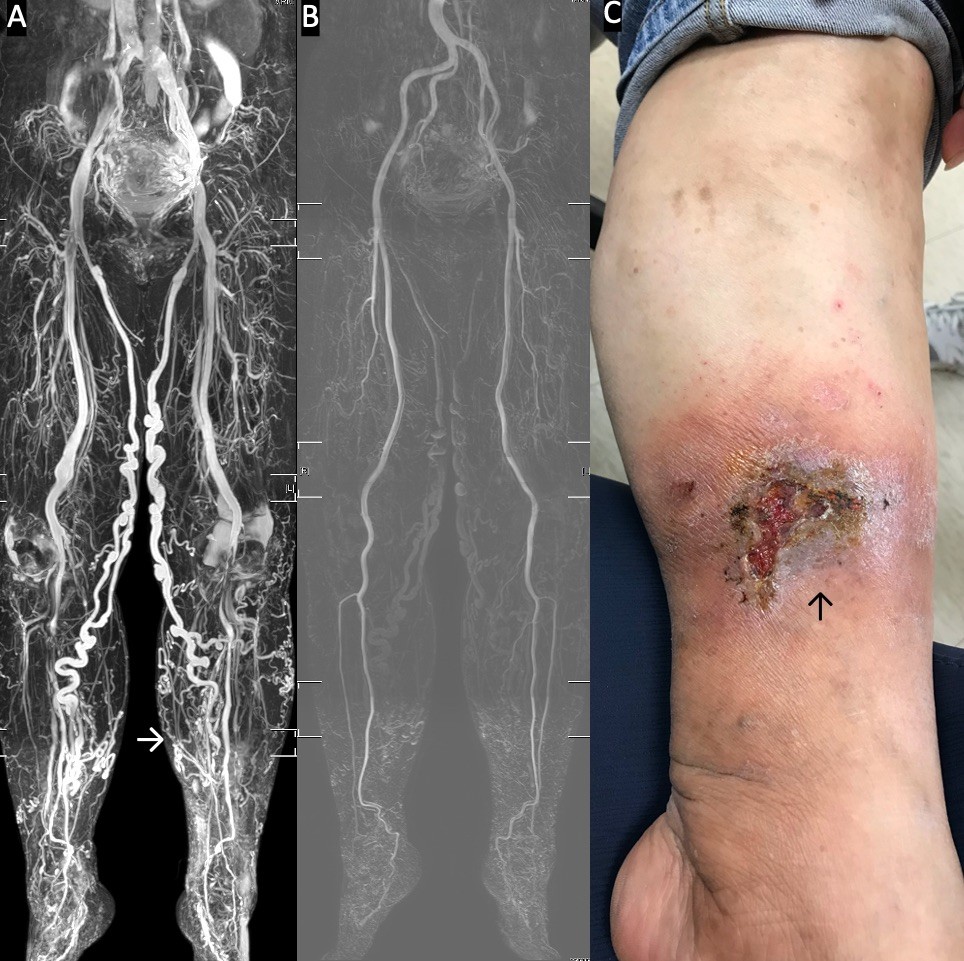

Stasis Leg Ulcers: Venous System Revises by Triggered Angiography Non-Contrast-Enhanced Sequence Magnetic Resonance Imaging

簡言之,就是把我們醫院用 TRANCE MR來輔助足部慢性傷口(特別是靜脈傷口)的經驗與大家分享。